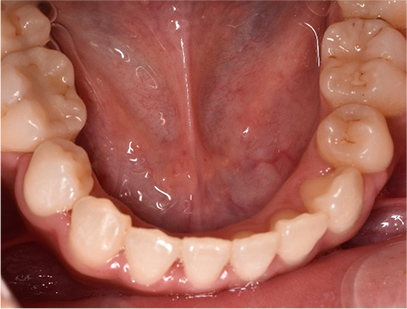

治療後

• 下側

治療前の写真と比べると上下の前歯は後方に下がりました。

そのために、鼻の下の膨らみもすっきりして、下唇も薄くなることができました。

治療期間は2年と6か月を必要としました。